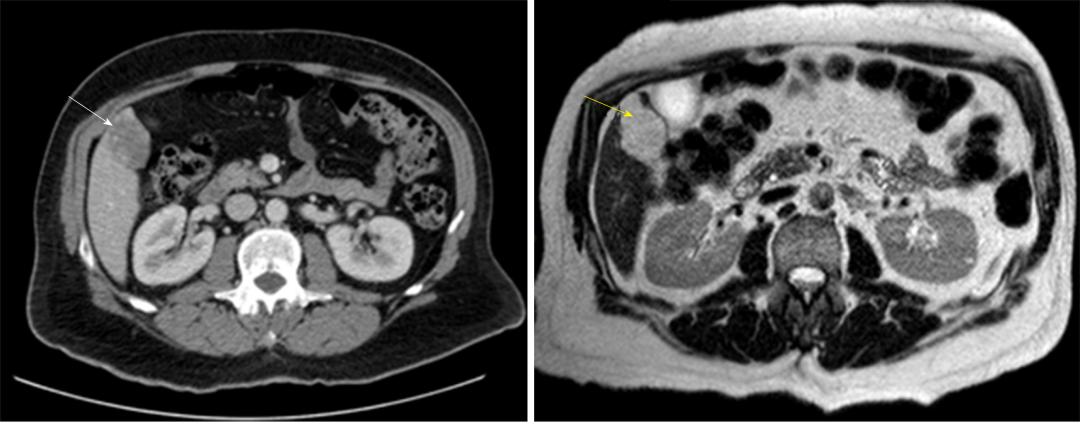

诊断 :HH的诊断目前主要依赖于影像学检查,多种检查手段联合应用可提高诊断准确率。常规首选超声检查,再结合CT、MRI以及数字减影血管造影检查等综合判断。

图3 腹部CT造影(白色箭头)和MRI T2加权扫描(黄色箭头)